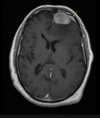

Epidural Hematoma

- Signs

- CT scan

Signs:

- headache

- mental status abnormalities

- loss of consiousness with brief lucid interval before subsequent decline

CT scan:

- bioconvex lens between skull and out margin (dura)